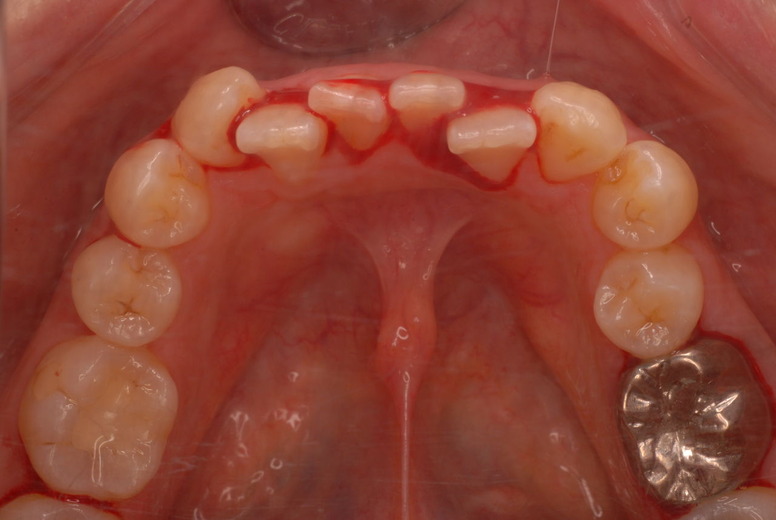

親知らずを取ることを嫌がる方が多いのですが、もし親知らずとその隣の14歳大臼歯の間に虫歯ができたり歯周病を罹患した場合、どれほど治療が大変で再発も起こりやすいか理解できない方がおおいのです。

写真左下の親知らずが痛くなり抜歯しました。その後歯茎を除去して虫歯を露出させる処置を二回ほどしています。

レントゲンでは小さいですが、こう言う虫歯が一番怖いのです。

治療の成功率は極めて悪くすぐ再発しやすいのです。